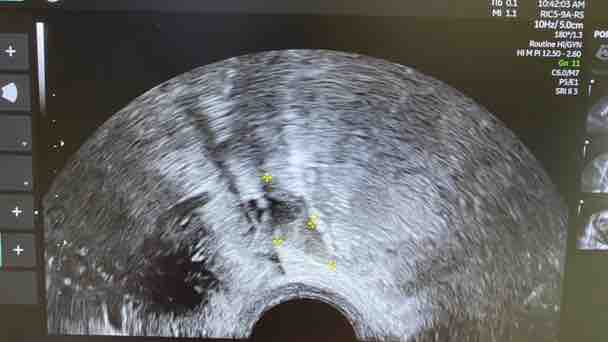

Ecosonografía transvaginal: Se visualiza útero en AVF, Heterogéneo de aspecto adenomiotico, en cara anterior de útero adenomioma mide 4,56 x 2,23 cm y en cara posterior se visualiza a nivel de istmo mioma de pequeño volumen, Ovario derecho se visualiza tumoración compatible luteoma, a nivel se unión rectosigmoidea se observa placa endometriosica que mide 2,22x 0,8 cm, signo de slicing negativo, Torus y ambos ligamentos uterosacros dolorosos a la exploración.

Susana, es mi prima, una joven de 32 años de edad, quien después de pasar mucho tiempo con fuertes dolores pélvicos hipogastrio de moderada intensidad, el cual no mejora con analgésicos-antiflamatorios, así mismo sangrado uterino irregular, maneja escala del dolor según funciones pélvicas: Dispareunia: 10/10pts, Disquecia: 10/10 pts, Dispareunia: 9/10 pts, Disuria: 10/10 pts. e intolerancia a los alimentos, el cual ha deteriorado su calidad de vida y actividades cotidianas. Le han descubierto, visualizando el útero en AVF, el cual es Heterogéneo de aspecto adenomiotico, en cara anterior de útero adenomioma mide 4,56 x 2,23 cm y en cara posterior se visualiza a nivel de istmo mioma de pequeño volumen, Ovario derecho se visualiza tumoración compatible luteoma, a nivel se unión rectosigmoidea se observa placa endometriosica que mide 2,22x 0,8 cm, signo de slicing negativo, Torus y ambos ligamentos uterosacros dolorosos a la exploración.